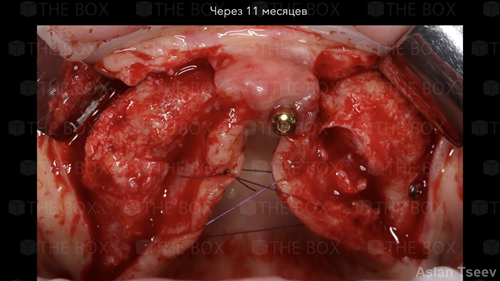

Infra bony defect one wall defect follow up 18 months show regeneration of buccal bone and interdental defect utilizing allograft bone substitute